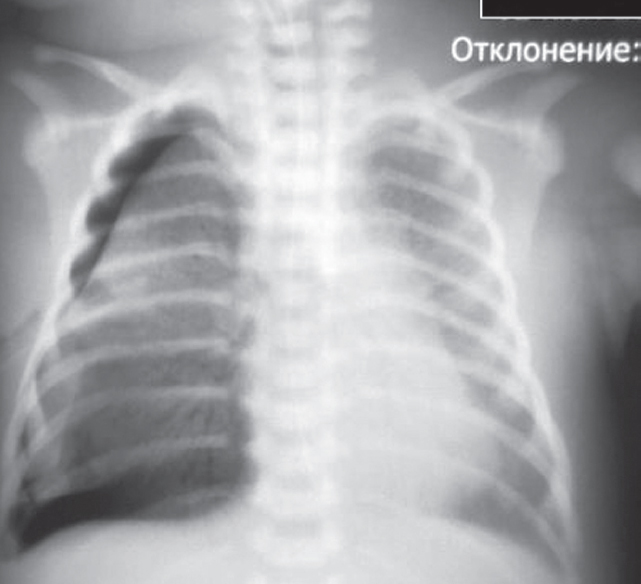

From birth, the child was in a moderately severe state due to respiratory distress (moderate retraction of the intercostal space, grunting breathing, and tachypnea of up to 60 breaths per minute), which required non-invasive artificial lung ventilation (ALV; nasal continuous positive airway pressure [nCPAP]) from the first minutes of life [2]. The radiograph showed signs of transient tachypnea (Fig. 1).

Fig. 1. Chest X-ray of newborn with clinical signs of respiratory distress 2 hours after birth

Рис. 1. Рентгенограмма органов грудной клетки новорожденного с клиническими признаками респираторного дистресс-синдрома через 2 ч после рождения